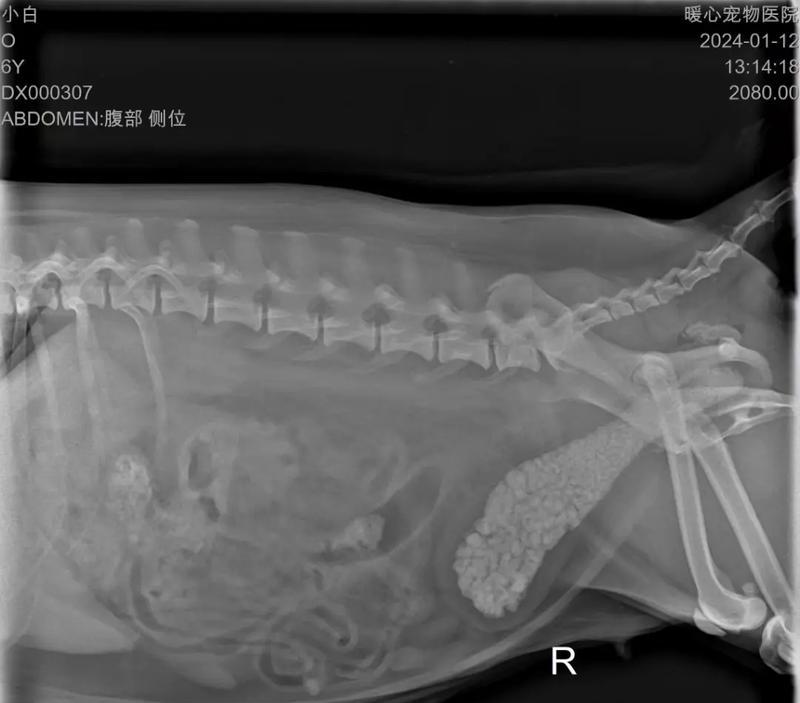

7.腹部触感异常:当你摸摸你的狗狗的腹部时,如果感觉到固体物质,可能是结石的存在。